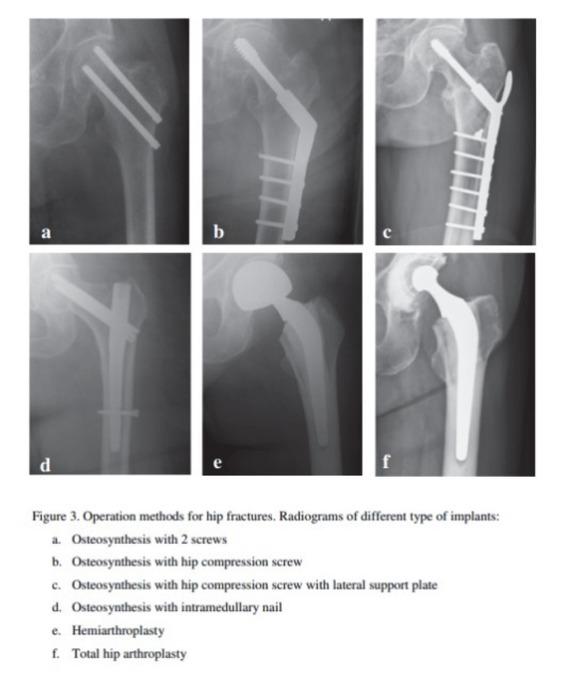

When the proximal femur is fractured, the tension of surrounding tendons and muscle will often lead to dislocation of the fracture ends, which prevents skeletal healing. Surgical treatment of hip fracture involves surgical implants to fix the ends of the femur in their anatomical correct position to enable healing. There is a multitude of different surgical implants used for hip fracture repair, but the implants most commonly used can be categorized in three broad categories: hemiarthroplasty and total hip arthroplasty, cannulated screws and hip compression screws (Fig. 1 and 2).

Plain film X-rays of hip fractures treated with different surgical implants. From Gjertsen (15). Reproduced with permission.

In hospital, resistance on the side of the body with the fractured hip was lower than the side with the unfractured hip, 496 (SD 98) ohm vs 527 (SD 101) ohm, P=0.0007. Table 2. The limit of agreement was wider in hospital compared to at follow-up, indicating that fracture and surgery affected BIA measurements. Figure 3 and 4. The difference in resistance or reactance between fractured and non-fractured hip did not vary by type of surgical implant, either during hospital stay or at follow-up.

Our results indicate that BIA is not affected by type of surgical implant of the three categories we examined. Hip arthroplasty, cannulated screws and compression hip screws have different masses and placement in the hip region. We believe that if the shape and the approximate shape of the different tissues of bone, fat and skeletal muscle mass are unchanged the type of surgical implant does not matter. It seems likely that more severe traumatic injuries where the shape of the hip is fundamentally changed or a tissue compartment is removed can result in larger changes in resistance or reactance.